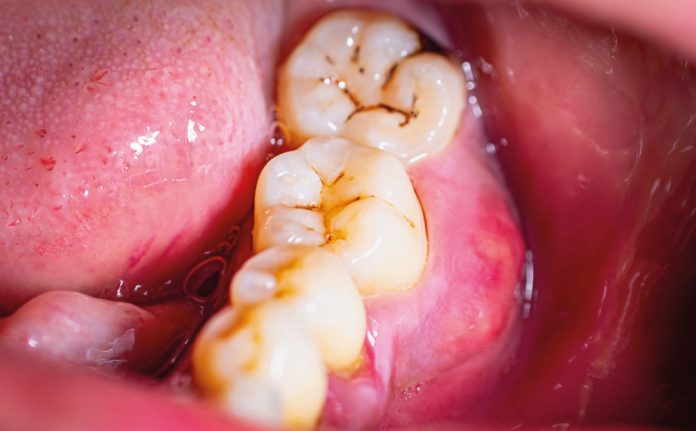

Le black stain rappresentano un problema estetico e clinico frequente in odontoiatria pediatrica e adolescenziale. Queste macchie dentali, spesso associate alla presenza di batteri cromogeni, si accumulano sulla superficie dei denti, causando discromie che possono influenzare negativamente l’autostima e la motivazione dei pazienti verso una corretta igiene orale (3, 4).

Negli ultimi anni, l’interesse verso approcci terapeutici alternativi ha portato all’esplorazione dell’uso di lattoferrina e probiotici in trattamenti combinati. La lattoferrina è una glicoproteina presente nel latte e in altri fluidi biologici, nota per le sue proprietà antimicrobiche e antinfiammatorie. Essa agisce sequestrando ioni ferro, fondamentali per la crescita dei microrganismi, inclusi quelli responsabili delle black stain, riducendo così la colonizzazione batterica e promuovendo un equilibrio favorevole del microbiota orale (2).